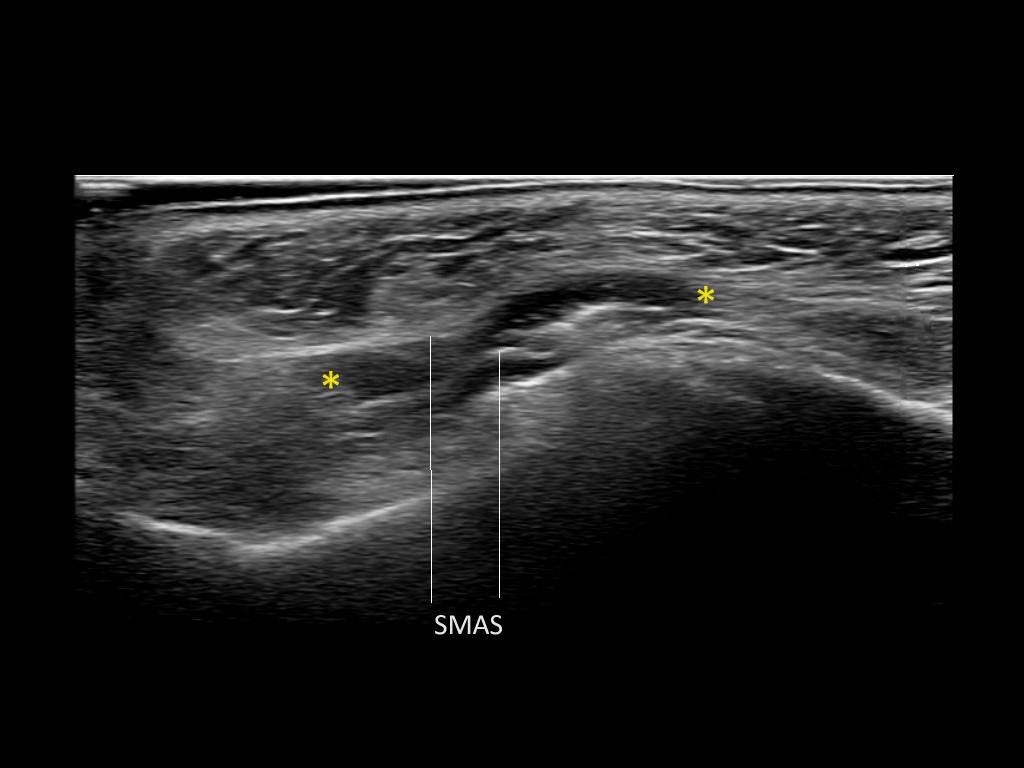

Filler deposits may end up unintentionally in the SMAS or fascial layers of the skin. Very often this will not lead to adverse events, however, adverse events ( nodules, migration / redistribution impaired muscle movement and smiling and malar edema) are are often related to filler ending up in the SMAS or fascia.

Study the first image to recognize the different layers. If you are sure about the layers, swipe to the second image to view the answer (if applicable).